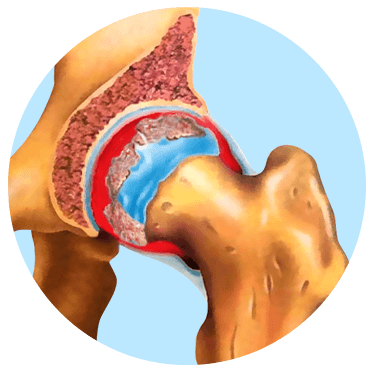

ЗДОРОВИЙ КУЛЬШОВИЙ СУГЛОБ

КУЛЬШОВИЙ СУГЛОБ УРАЖЕНИЙ ОСТЕОАРТРОЗОМ